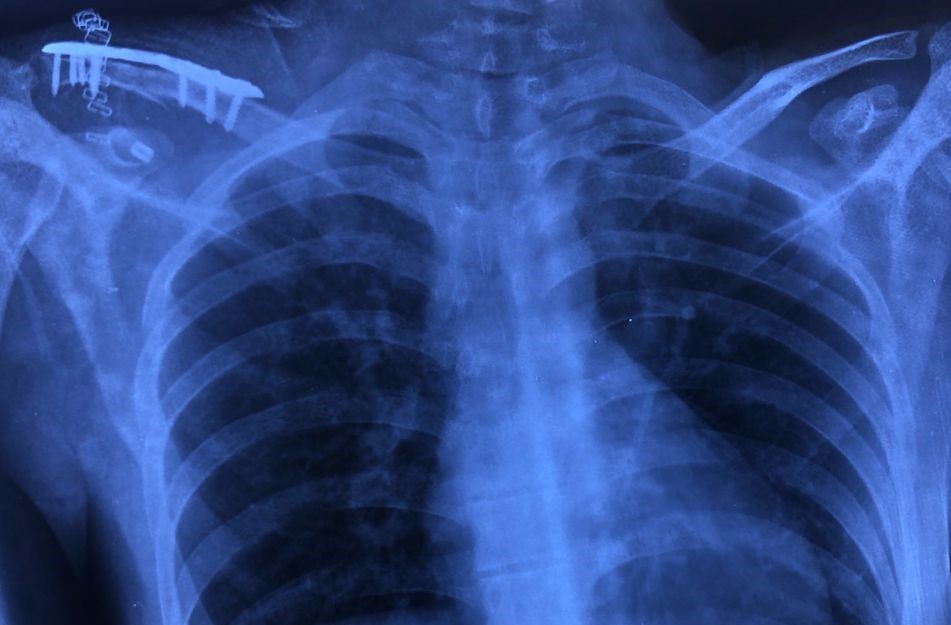

Under general anesthesia in beach chair position, a 5–7 cm vertical (“bra-strap”) incision was made from the tip of the coracoid process to anterosuperior aspect of the lateral third of the clavicle. Medial and lateral flaps were developed. The deltotrapezial fascia was then incised perpendicular to the skin incision and released from the clavicle. The fracture ends and coracoid was exposed. Dissection medial to the coracoid was avoided to prevent inadvertent damage to neurovascular structures. A tunnel was made at the coracoid base centrally about 1.5 cm from its tip using a 2.5 mm drill bit. Another bony tunnel was made in the clavicle just above the coracoid slightly anterior to the midline. Then, an EndoButton loaded with ethibond suture no. 5 was passed under the coracoid and the clavicle tunnel in a retrograde fashion so that the EndoButton flipped on the undersurface of the coracoid and two ends of the suture come out of the clavicle which were later tied to the distal clavicle plate. The fracture ends were then reduced and fixed with anatomically pre-contoured locking distal clavicle plate, as shown in Fig. 1.

Figure 1: Clavicular fracture fixation done with anatomically pre-contoured plate and ligamentous reconstruction done with tunneled suspensory device (EndoButton).

Figure 2: Immediate post-operative radiograph of the unstable lateral end clavicle fixed with our surgical technique.

Proper hemostasis was achieved and wound was closed in layers. No drain was applied. The arm was immobilized in an arm pouch. Immediate post-operative radiograph was done (Fig. 2).